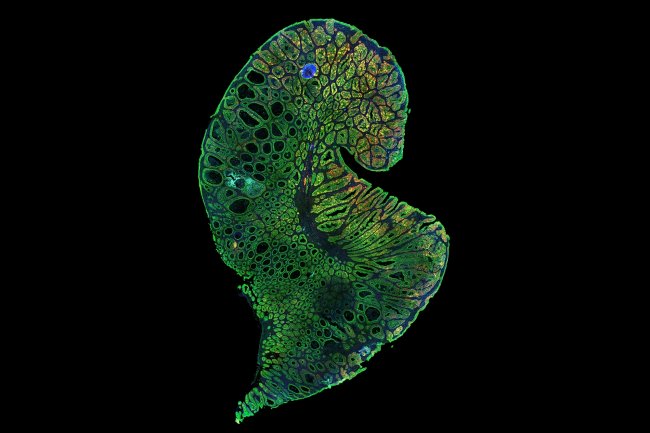

How does the body renew itself? How do cancer cells use the same or similar processes to form tumors and spread throughout the body?...